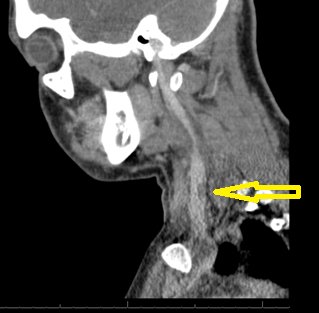

On initial evaluation, T 37.6 ᵒC, BP 93/60 mmHg, HR 146/min, SpO2 98% on 2 L of nasal cannula oxygen. He is a well-nourished young male in acute distress. He had bilateral tonsilar enlargement, swollen uvula with bilateral anterior cervical lymphadenopathy. His cardiac exam revealed tachycardia, regular rhythm with no murmurs. His lung exam revealed bilateral air entry with no added sounds. His abdomen was soft. No skin rashes were noted and his neurological examination was non-focal. Initial laboratory investigations showed acute kidney injury, lactic acidosis, leukocytosis, lymphopenia and thrombocytopenia. CXR was normal. EBV serology, throat culture, respiratory virus panel and HIV and cocci serology were negative. Blood cultures were drawn and the patient was volume resuscitated. A working diagnosis of sepsis secondary to EBV pharyngitis was made. On day 1 of hospital stay, he reported cough, CT chest showed multifocal pneumonia suggesting hematogenous spread of infection. Given the septic embolic presentation and sore throat, Lemierre’s disease was considered. He was started on broad spectrum antibiotics. CT scan of the neck showed a partially occlusive thrombus in the left internal jugular vein. Blood culture eventually grew F. necrophorum and was sensitive to amphicillin-sulbactam and meropenem. Antibiotic therapy was de-escalated to amphicillin-sulbactam. He remained febrile for five days even after the start of antibiotic therapy. Repeat blood cultures were negative. The patient was discharged home on 4 weeks of IV antibiotic therapy. On follow up after 4 weeks, he was doing well and antibiotic was switched to oral to complete 6 weeks of therapy.